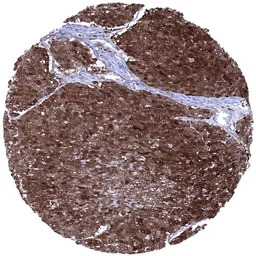

IHC-P analysis of human rectum mucosa tissue section using GTX04453 Cystatin A antibody [MSVA-461M] HistoMAX.

Cystatin A immunostaining is always absent in epithelial cells of the colon.